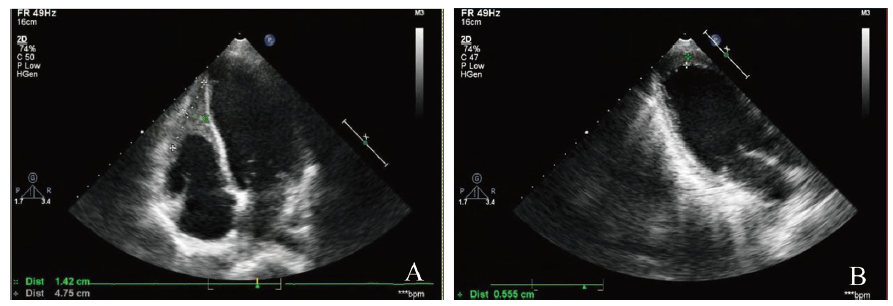

心电图示窦性心律,缺血性ST改变(V1-V4导联水平型压低0.05 ~ 0.35 mV)V1-V3导联呈QS型,见图1。心脏彩色多普勒超声(彩超)示右心室心尖部心腔内探及弥漫弱回声48 mm×14 mm,致右心室心尖部心腔狭小;左心室心尖部近前壁也可探及弥漫弱回声,厚约6 mm;左心室增大、节段性室壁运动异常;二尖瓣脱垂并轻度返流;三尖瓣轻-中度反流;主动脉瓣及肺动脉瓣轻度反流;少量心包积液;左心室收缩功能偏低(LVEF 52%),见图2。B超示两侧睾丸肿大(左54 mm×21 mm,右57 mm×23 mm),内部回声不均匀,未见明显光团或暗区、占位性病变,两侧附睾未见明显异常。腹部彩超+泌尿系统彩超未见异常。

图2 一例Loffler心内膜炎患儿心脏彩超图

A:右心室心尖部心腔内探及弥漫弱回声;B:左心室心尖部近前壁也可探及弥漫弱回声

本例患儿心脏彩超提示Loffler心内膜炎(右心室及左心室心尖部心腔内可探及弥漫弱回声),即EOS增多浸润损害了心脏心内膜而表现出来的一种影像学结果,还有心电图的改变及心功能改变,这也是符合文献中所提及的。有学者认为对于白细胞>100×109/L或HE伴有心肌损害,特别是Loffler心内膜炎,这都提示差的预后和高的病死率,其中EOS心肌炎和心内膜纤维化所导致的心力衰竭是死亡的常见原因[1,2]